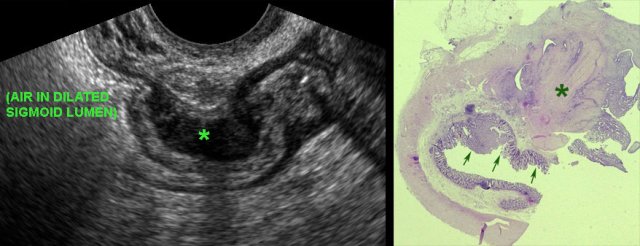

TVUS detects small sigmoid CA in patient with massive colonic obstruction. TVUS detects small sigmoid CA in patient with massive colonic obstruction.

Sigmoid carcinoma

A 66-year old woman presented with progressive bloating and constipation. CT showed massive colonic dilatation, but pelvic CT (not shown here) was of low quality due to two hip prostheses.

US confirmed multiple, strongly dilated, air-filled large bowel loops, but was otherwise non-diagnostic.

TVUS demonstrated a small, stenosing sigmoid carcinoma with concomitant desmoid reaction (*) in the surrounding fat.

Adenomatous polyp in the sigmoid, detected by TVUS. Adenomatous polyp in the sigmoid, detected by TVUS.

Adenomatous polyp

A colonic polyp (arrow) was seen both on CT and at colonoscopy, however due to adhesion-related kinking, the polyp was out of reach for biopsy.

Surgeons wanted more proof before proceeding to laparoscopic resection.

TVUS showed an ovoid, solid, well-defined, inhomogeneous, hypervascular, intraluminal mass (arrows) with a diameter of 1.5 cm.

Segment resection was done, histology showed a malignant adenomatous polyp.